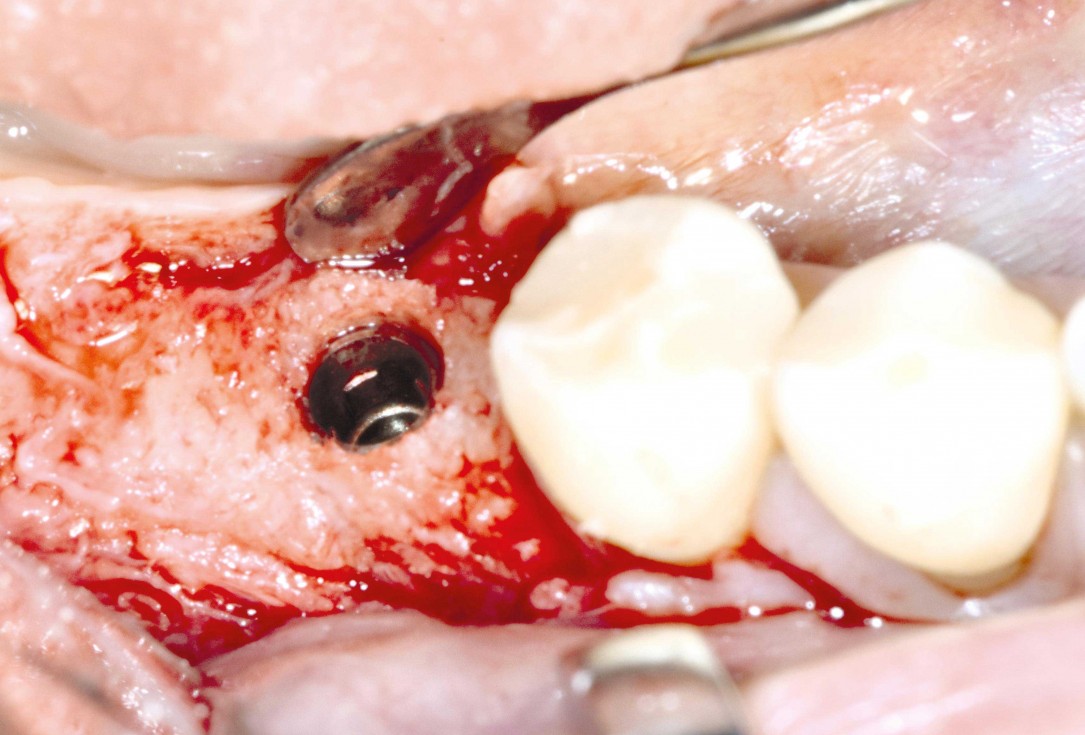

Three implants placed in a narrow posterior mandible